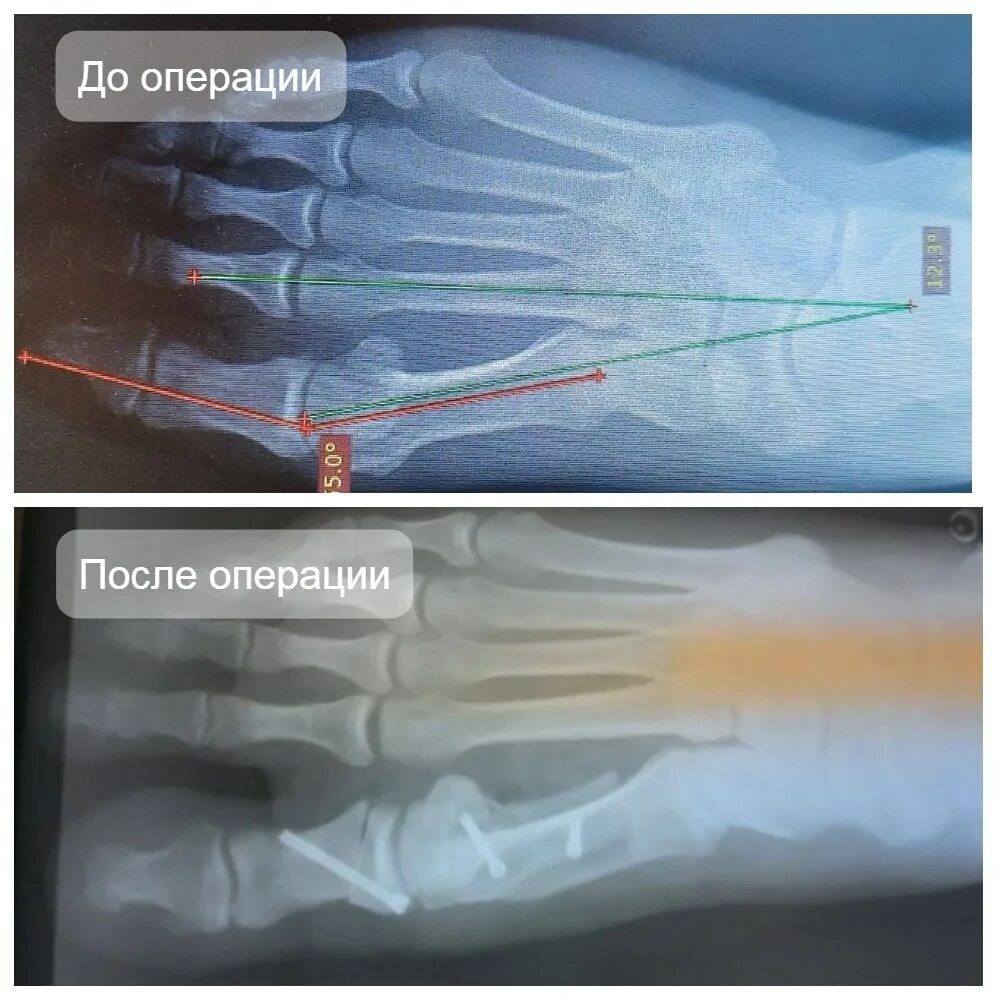

Операция на косточки как называется